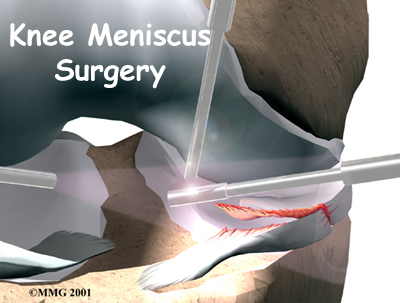

Meniscal Surgery

The meniscus is very important to the long-term health of the knee. In the past, surgeons would simply take out part or all of an injured meniscus. But today's surgeons know that removing the meniscus can lead to early knee arthritis. Whenever possible, they try to repair the tear. If the damaged area must be removed, care is taken during surgery to protect the surrounding healthy tissue.